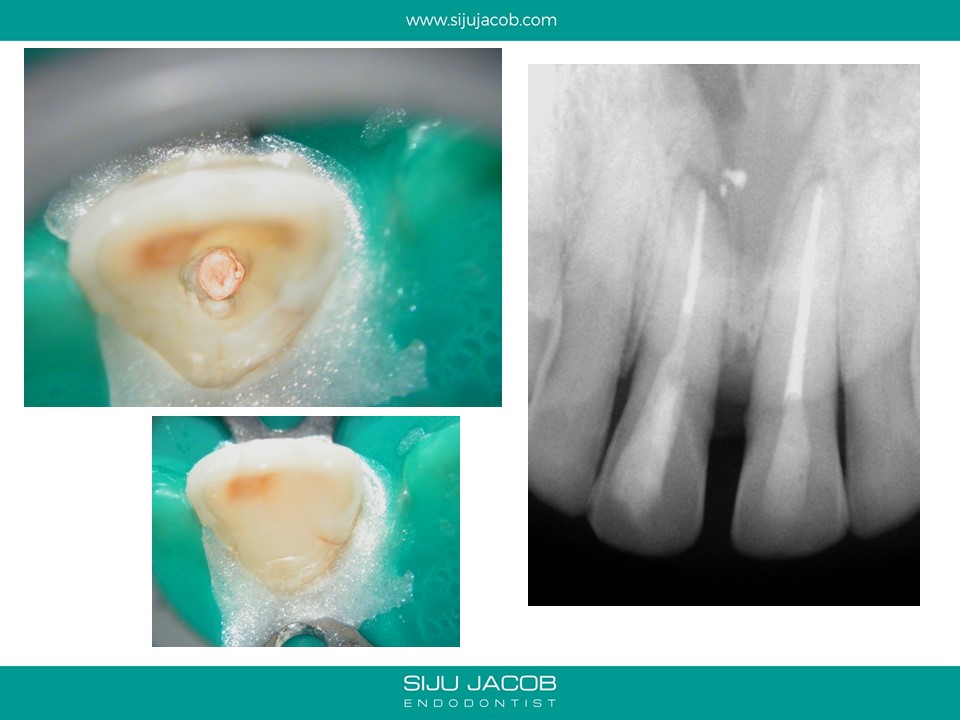

This was a case which was started by another clinican. A Naso-palatine cyst was mis-diagnosed as lesion of endodontic origin. The clinician opened up two central incisors, broke an instrument in one, couldn’t locate the canal (nearly perforated) and then referred the case.